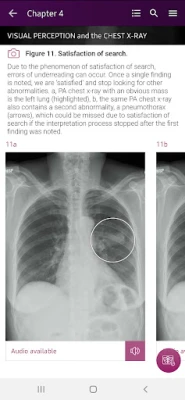

• Help you develop the skill of identifying all chest x-ray pathologies, not only the obvious.

How To’s – 34 step-by-step guides, with annotated x-rays, to illustrate key skills needed to confidentially interpret chest x-ray.

Visual Searches – 8 visual guides to illustrate the sequential checks that should be performed in a visual search of given anatomical structure or radiological zone on a chest x-ray.